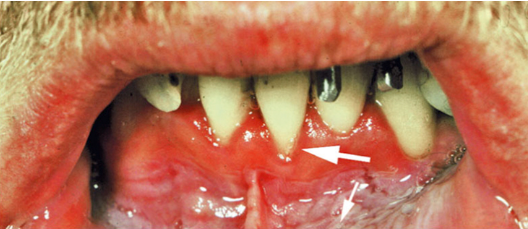

<p>8. Looking at Fig. 5.25, what gingiva is edematous?</p><p>a. Gingival margin</p><p>b. Attached gingiva</p><p>c. Interdental papilla</p><p>d. a. and c.</p>

8. Looking at Fig. 5.25, what gingiva is edematous?

d. a. and c.

<p>49. What is a possible cause of the recession seen in Fig. 5.30?</p><p>a. Labial frenum attachment</p><p>b. Chewing tobacco</p><p>c. Toothbrushing</p><p>d. All of the above</p>

49. What is a possible cause of the recession seen in Fig. 5.30?

d. All of the above